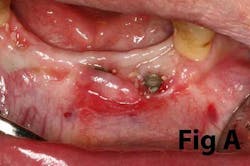

Case No. 1

Case No. 2